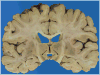

Context: Autopsy evaluation of the brain of a patient with frontotemporal dementia (FTD) can be daunting to the general pathologist. At some point in their training, most pathologists learn about Pick disease, and can recognize Pick bodies, the morphologic hallmark of Pick disease. Pick disease is a type of frontotemporal lobar degeneration (FTLD), the general category of pathologic process underlying most cases of FTD. The 2 major categories of pathologic FTLD are tauopathies (FTLD-tau) and ubiquitinopathies (FTLD-U). Pick disease is one of the FTLD-tau subtypes and is termed FTLD-tau (PiD).